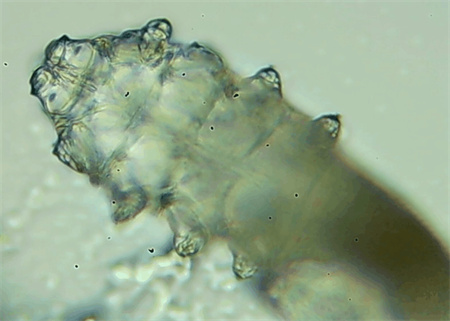

把玻片放到顯微鏡下觀察,通過電腦實時傳送的畫面,可以查看到這些拔下來的睫毛上是否有螨蟲。

結(jié)果,有6個人拔下來的睫毛上都發(fā)現(xiàn)了螨蟲。

這種螨蟲叫做蠕形螨,他們通常呈乳白色、半透明的細長狀,擁有四對腳。它們跟被子上的塵螨可不是同一種。

這些蠕形螨主要寄生在面部、頭皮、眼睛的睫毛毛囊、睫毛皮脂腺,以及瞼板腺里,以睫毛囊上皮細胞、腺體內(nèi)脂質(zhì)為食物。因此,即使經(jīng)常換洗床單、衣物,也可能會有蠕形螨。